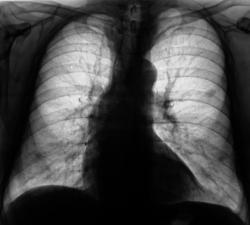

При расшифровке флюорограграмм (2007) пациент был "взят на контроль" - на уровне 4 ребра слева обнаружена крупноочаговая тень.

Провели рентгенографию в прямой стандартной проекции. С учетом "неубедительности" теневой картины "решили понаблюдать".

Зафиксировано увеличение тени в размерах. Произведена рентгенография в прямой стандартной проекции.

Было высказано предположение о наличии "маленького периферического рака", зафиксирована "линзеподобная тень" паракостально. Пациент направлен на консультацию в онкологический диспансер.